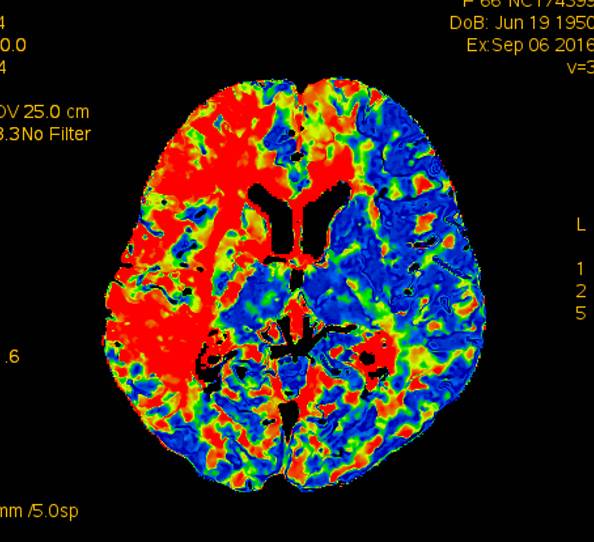

术前CTP示:右侧大脑半球灌注较差。

术后2个月患者未再诉右眼黑曚。复查CTP示:颅内灌注明显改善。

术前灌注成像,右侧大脑半球灌注较差。

此次分享两例颈动脉闭塞复合手术开通病例。第一例为颈内动脉长段闭塞,从颈内动脉起始段开始闭塞。患者术前存在眼动脉缺血事件及右侧半球灌注不足。颈内动脉剥脱后,颈内动脉可淡淡显影,为微导管通过创造条件。微导管通过后,顺利完成球囊扩张及支架植入,完全开通右侧颈内动脉。第二例为右侧颈总动脉闭塞患者,虽有颈外动脉代偿,但仍存在TIA及右侧大脑半球灌注不足。经颈动脉内膜剥脱后,造影可见颈总动脉显影,但管腔严重不规则,经球囊扩张及支架植入后,颈总动脉显影好。两例患者术后7天复查颈动脉CTA,均显示颈内动脉起始处较术后造影增粗。